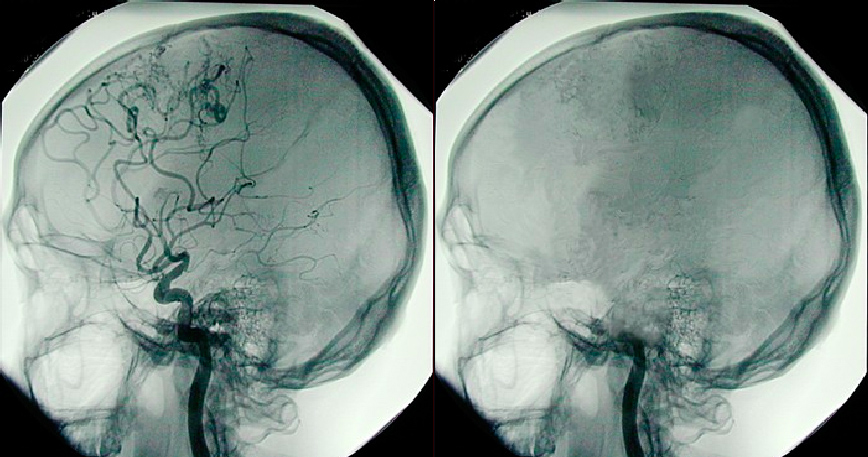

Side by side images of brains; one healthy one dead

A perfusion scan shows a normal brain (right) versus a brain that has died.

Brain death. Brain death is different from persistent vegetative state because the entire brain, including the brainstem, is dead. A person who is considered brain dead is considered legally dead, even if his or her heartbeat and breathing are maintained through artificial devices. One of the most common causes of brain death is anoxic damage, caused when oxygen can’t reach the brain.

There are several tests doctors use to determine if brain death has occurred. One is to screen for drugs and alcohol that can cause symptoms similar to brain death. When these causes are ruled out, doctors check for basic reflexes such as eye movement in response to light and gagging when the back of the throat is touched. Finally doctors run a perfusion scan to see if any blood is circulating in the brain and an electroencephalogram to look for electrical activity in the brain. If neither circulation or electrical activity is present, brain death is confirmed.